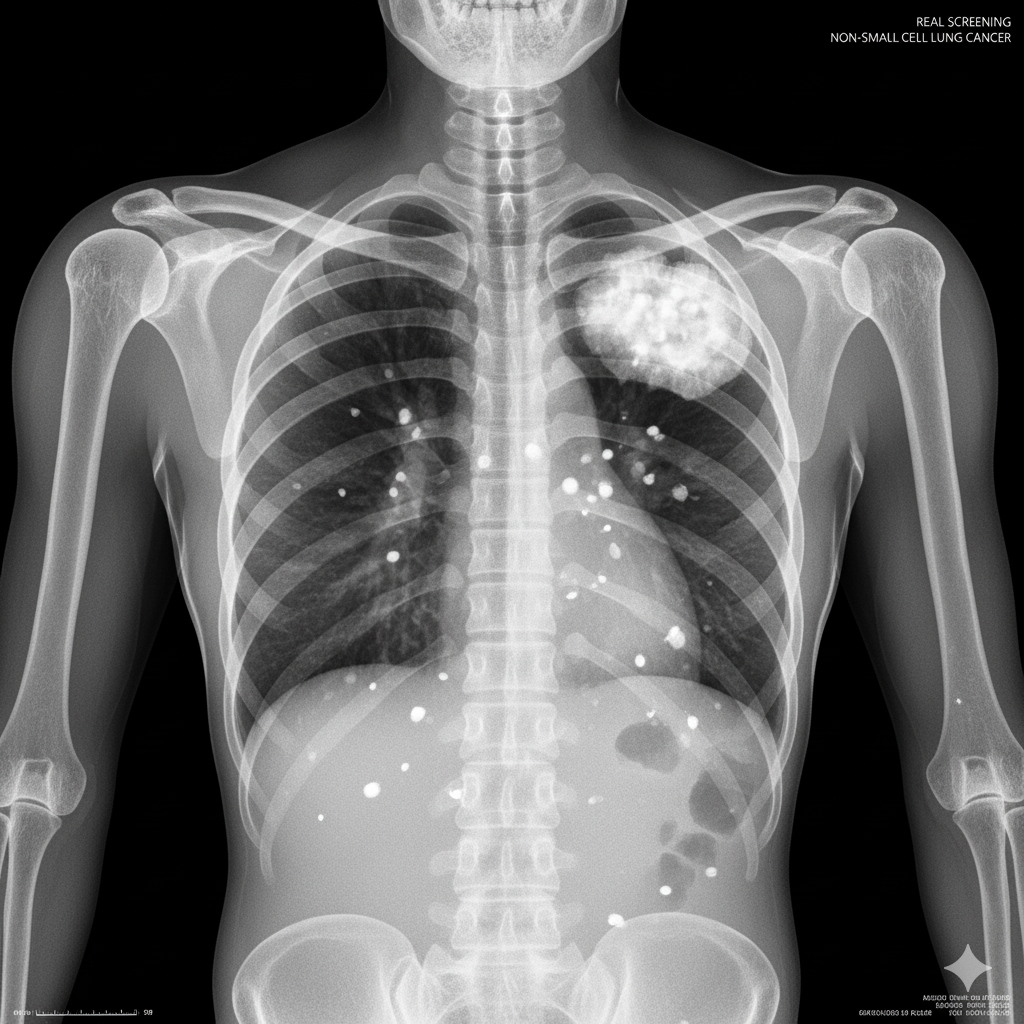

Nadváha nebo obezita je dnes uznávána jako druhá největší preventabilní příčina rakoviny po kouření. Nadbytečný tělesný tuk není neaktivní; je to metabolicky aktivní tkáň, která produkuje hormony a zánětlivé signály. To může v těle vést k prostředí, které podporuje růst a dělení rakovinných buněk.

Toto zvýšené riziko se netýká vzácných onemocnění. Je spojeno s nejméně 13 různými typy rakoviny, včetně některých z nejběžnějších. Pro ženy to zahrnuje rakovinu prsu (po menopauze) a rakovinu dělohy (endometria). Pro muže je hlavním problémem rakovina tlustého střeva a konečníku. Mezi další druhy rakoviny spojené s obezitou patří rakovina ledvin, jater, slinivky břišní a jícnu.